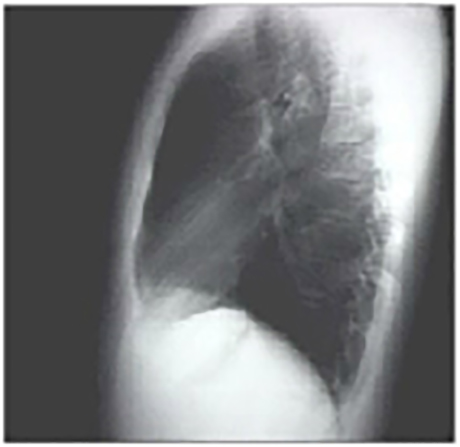

Lateral view

These chest X rays are normal. The PA view demonstrates no abnormalities of the bone structures, lung fields, or cardiac silhouette. The right and left heart borders are normal as are the great vessels superior to the cardiac silhouette. Note the cardiothoracic ratio is also normal, that is, it is less than 50%. The lateral view is normal, with no evidence of chamber enlargement including the normal anterior shadow of the right ventricle and posteroinferior shadow of the left ventricle.